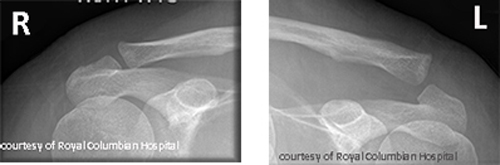

What are the types of AC joint injuries?

Sprain, subluxation (partial dislocation), and complete dislocation.

What causes AC joint injuries and how are they treated?

Fall on shoulder or sports impact; treated with sling or surgery if severe.

What are long-term complications of AC joint injuries?

Pain, arthritis, decreased ROM.

What is the normal range of the AC joint space?

Between 3 mm and 7 mm.